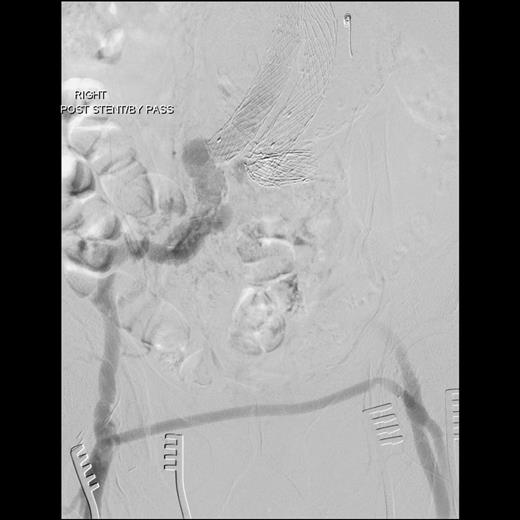

An 81-year-old gentleman with a background of ischaemic heart disease, hypertension, hyperlipidaemia, polycystic kidney disease and previous right hemicolectomy for bleeding diverticular disease, underwent EVAR 10 years ago. He was on yearly follow-up with computed tomography (CT) scan and latest CT in 2012 showed a type III endoleak with aneurysmal sac of 10 cm in size. Both common iliac arteries were long and tortuous. He was electively admitted for a diagnostic calibrating aortogram in our CT hybrid angiography suite (Toshiba Infinix VC-i). Intra-operatively, digital subtraction angiography (Fig. 1) showed significant type IIIa endoleak with component separation on the left iliac limb. The old stent graft was <20 mm away from the left renal artery proximally (lowest visceral artery). He was discharged the next day and re-admitted 2 weeks later for a staged operation. Decision was made for a combination of left renal artery chimney, aortouniiliac stent grafting and femorofemoral crossover bypass.

Digital subtraction angiography showing significant type 3a endoleak with component separationon the left iliac limb (black arrow). Both common iliac arteries were long and tortuous.